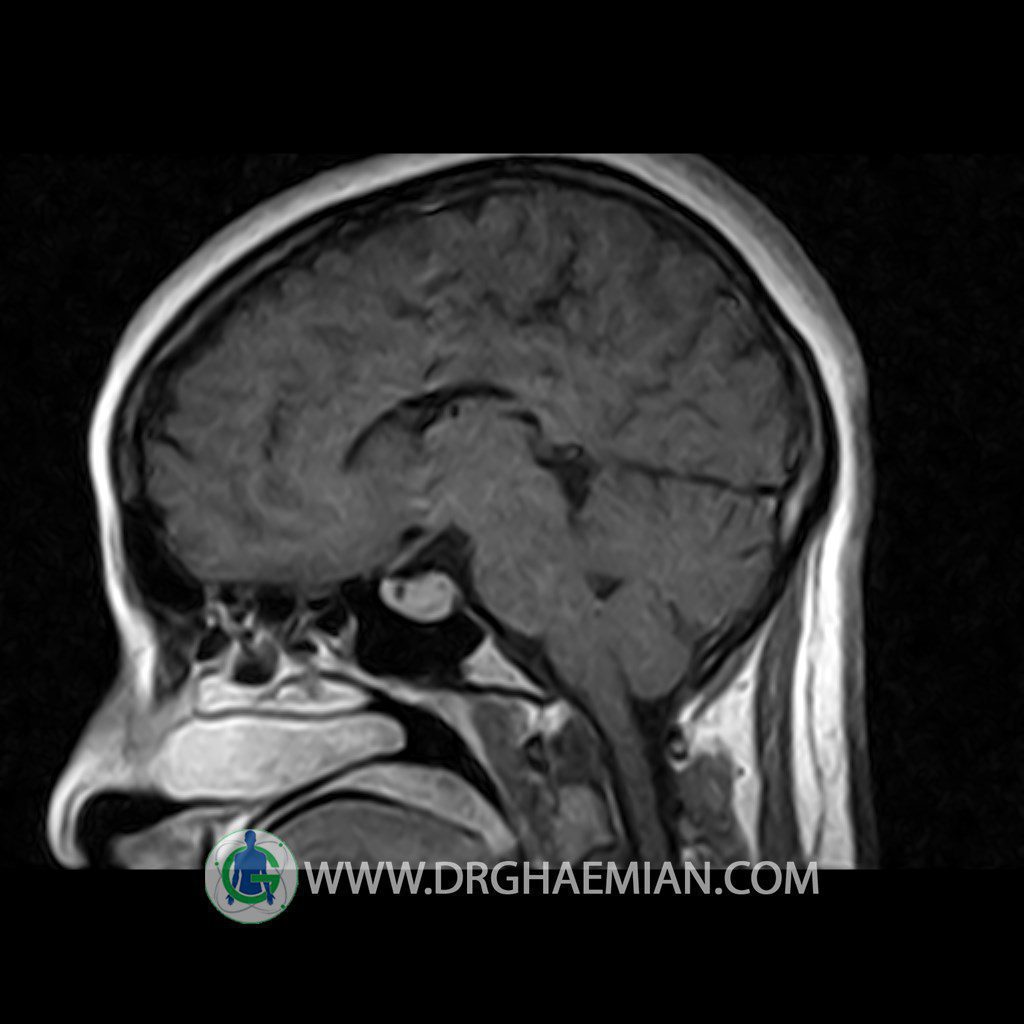

ام آر آی هیپوفیز یک روش تصویر برداری است که از غده هیپوفیز (غده ایی کوچک در مغز که هرومون ها و دیگر غدد بدن را کنترل می کند) و ناحیه های پیرامونش در مغز تصاویری ایجاد می کند. در این کیس سلای نسبتا خالی در ناحیه هیپوفیز بیمار مشاهده می شود.

HYPOPHYSIS MRI

Technique: Axial , coronal T1 , Axial , coronal , sagittal T2 , Axial, coronal T1 post Gd & 64 dynamic thin coronal slices.

The pituitary tissue shows normal , position, shape , size and homogeneous signal intensity both before and after contrast administration .

Anterior and posterior pituitary gland were normal .

It contains no circumscribed hypointense or hyperintense areas .

The infundibulum is centered and of normal size .

The optic chiasm and suprasellar spaces appear normal .

The cavernous sinus and imaged portions of the internal carotid artery and carotid siphon are unremarkable .

Evaluable portions of the neurocranium show no abnormalities .

The sphenoid sinus is clear and pneumatized .

Imaging of the hypothalamus after contrast medium administration was normal.

– Extension of suprasella cistern to sella with thin pituitary gland in floor of sella ( partial empty sella )

is seen